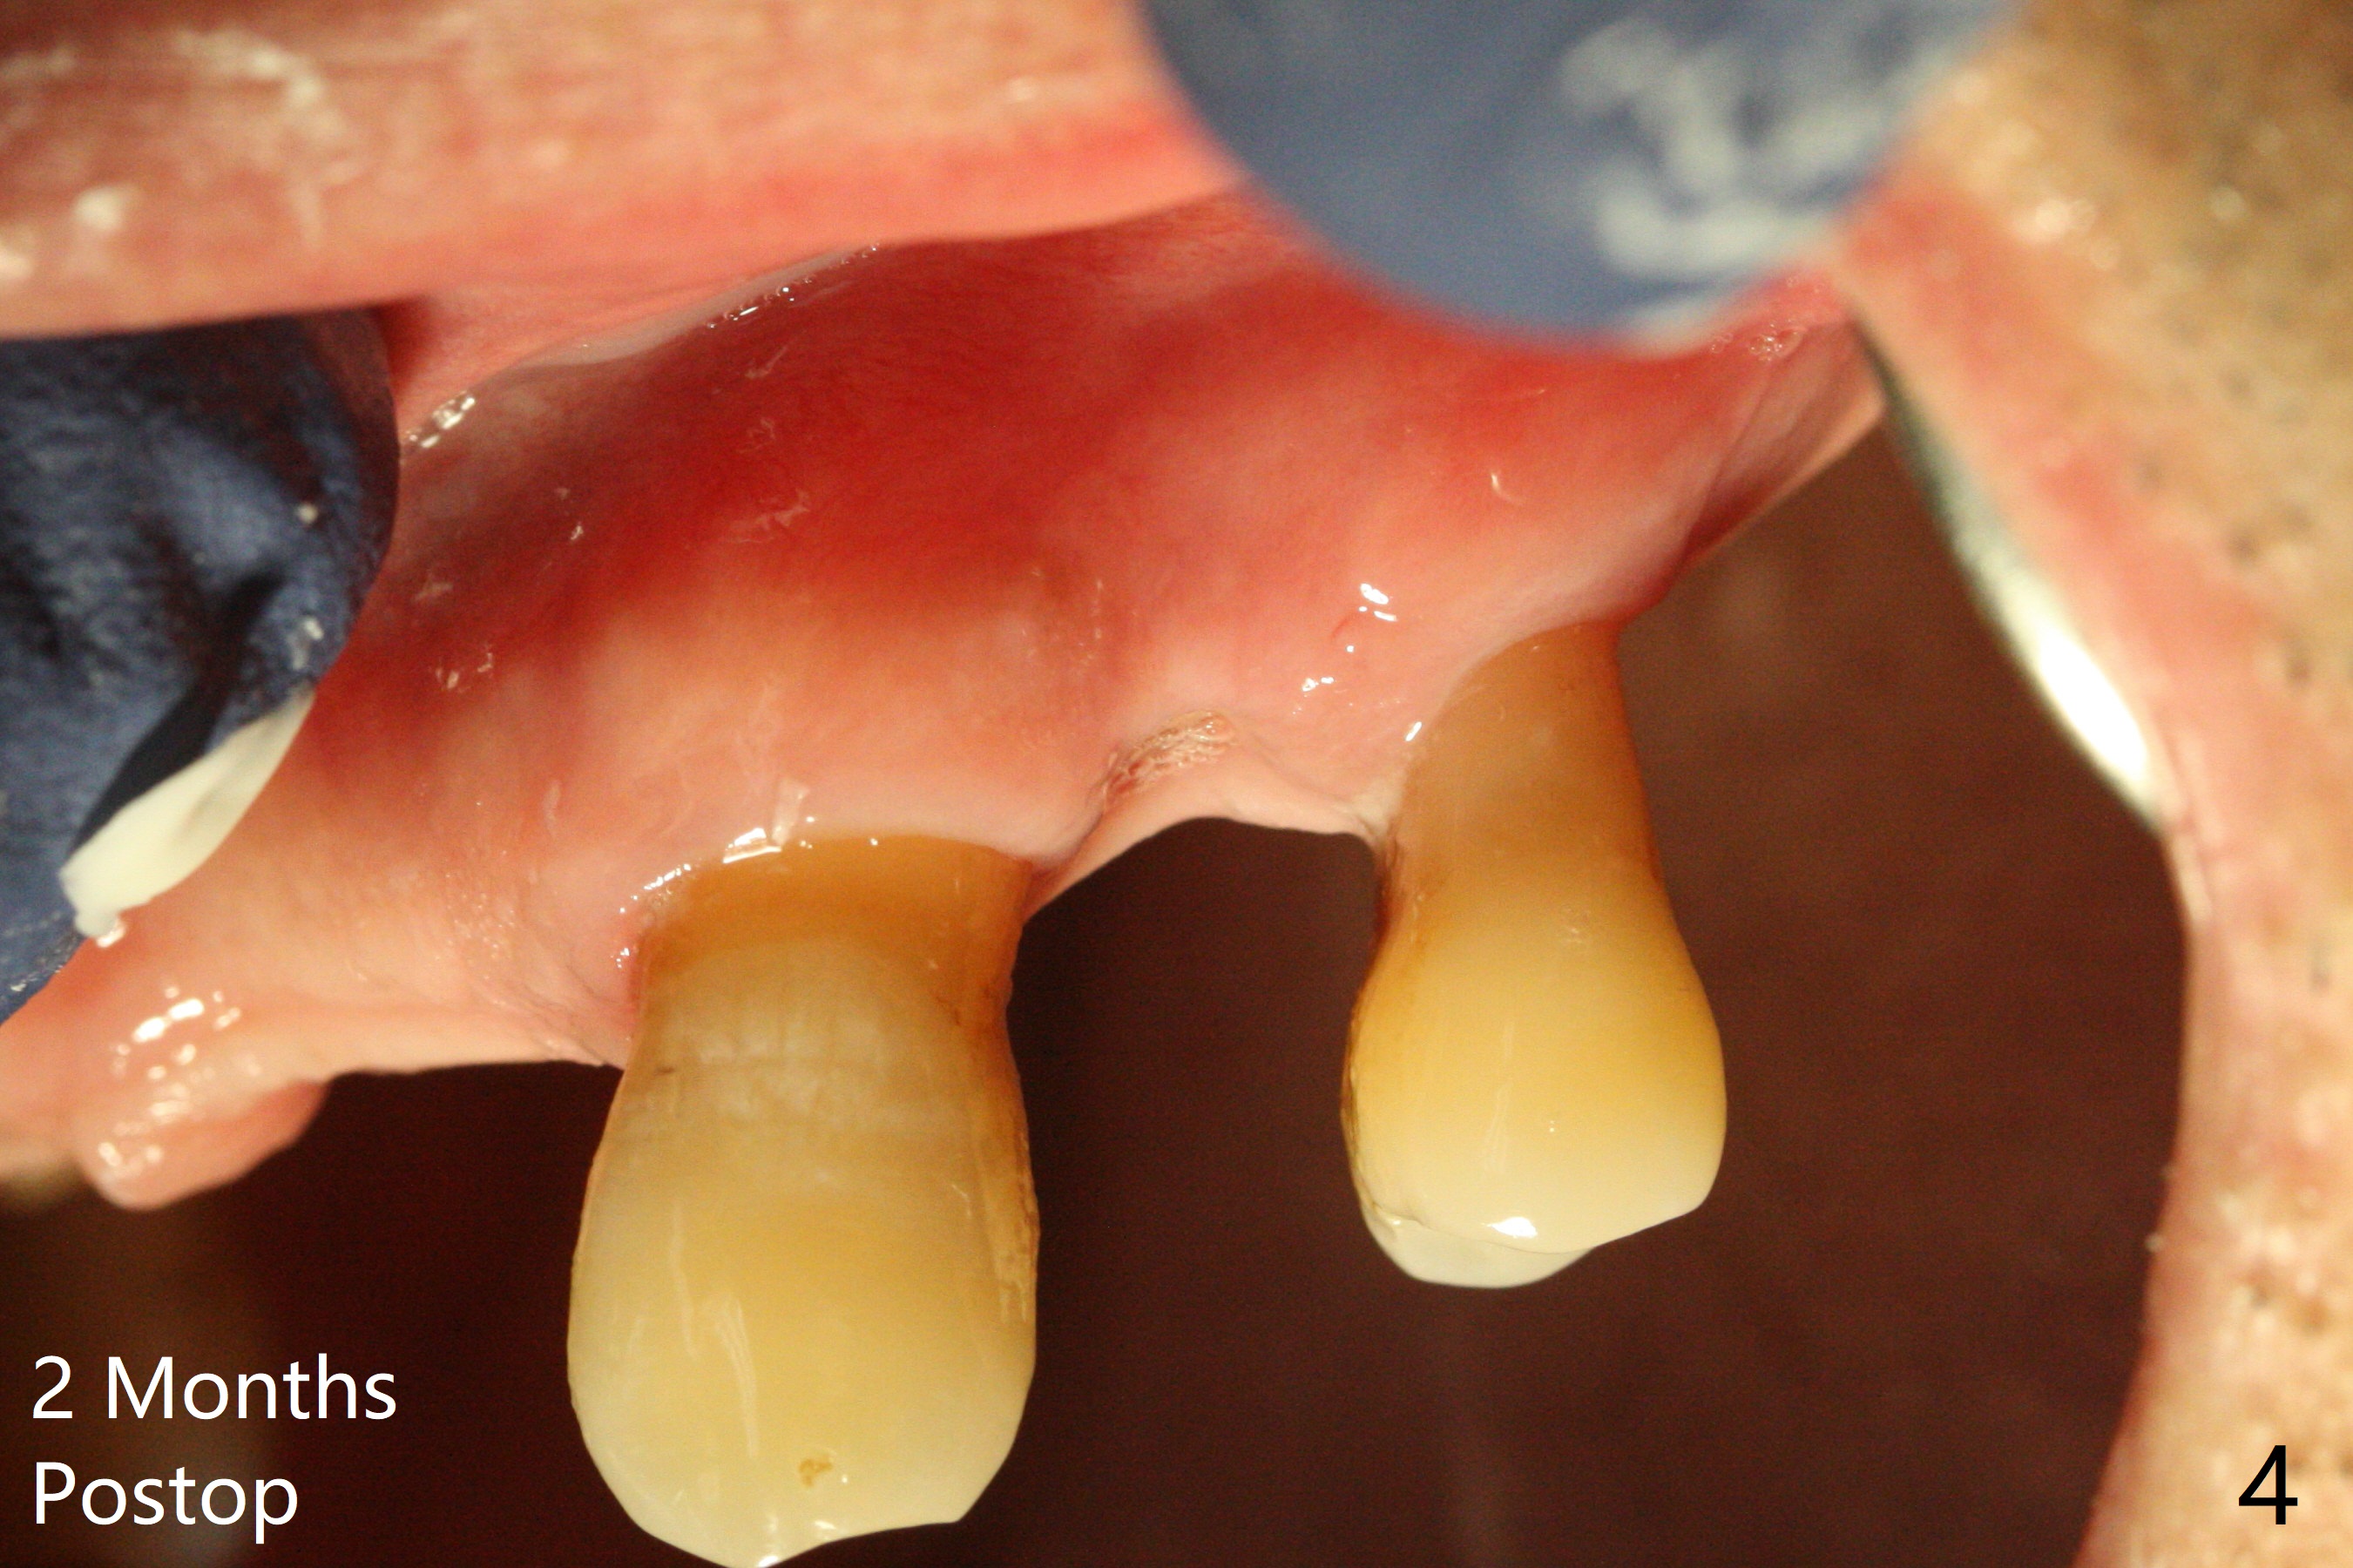

A 55-year-old man has been our patient intermittently for the last 15 years. Before removal of the tooth #12 with loss of the buccal plate (Fig.1), he requests bone graft for the health (strength) of the neighboring teeth (Fig.2 *). To keep the 6-month membrane in place longer, periodontal glue is used after suturing (Fig.3 (blue)). There is buccal collapse 2 months post socket preservation (Fig.4,5). Titanium mesh or Cytoplast should have been placed.